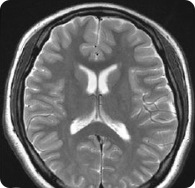

뇌 MRI (뇌 자기공명영상)

다양한 각도에서 뇌조직 확인

두개골 내부의 해부학적 구조를 세부하게 볼 수 있는 검사

뇌경색, 뇌종양, 치매 등의 뇌형태 이상을 초래하는 이상 소견을 확인